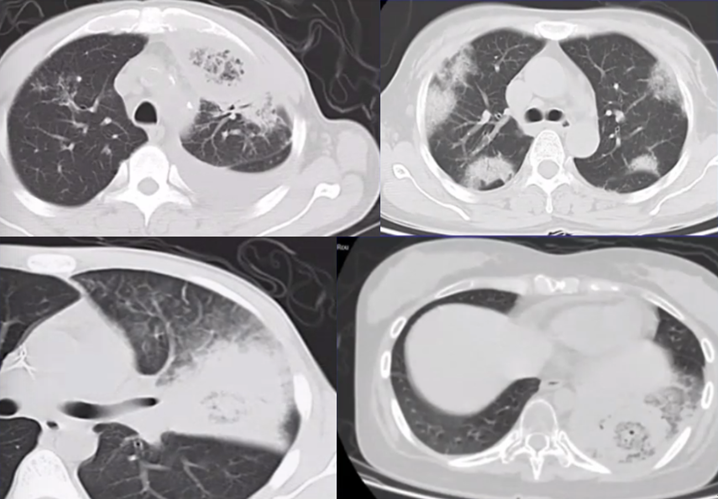

曲霉的破坏程度与曲霉菌丝生长相对成比例,其破坏范围形成的坏死、空洞及分隔均少于毛霉,而毛霉的破坏力更强。下图是一个结节,周边有晕征,说明病变是血管侵袭性,其中有很多小气泡,没有液平面,说明有菌丝的存在,菌丝固定了坏死物。但纵隔窗看到分隔特别粗大,小气泡特别大,说明坏死占的比例更多,坏死程度更严重,而菌丝的生长与坏死程度不成比例,所以是“坏死多菌丝少”,这是毛霉的特征。而曲霉感染则是“坏死多菌丝多”,坏死物相对固定,小气泡并未形成大的空洞。这也是曲霉和毛霉重要的鉴别点(图22)

图片

图22  毛霉和曲霉感染坏死、空洞的区别

注:A、B为毛霉所致病变,空洞内分隔粗大不均,空洞更大;C为曲霉所致坏死物固定,小气泡多。